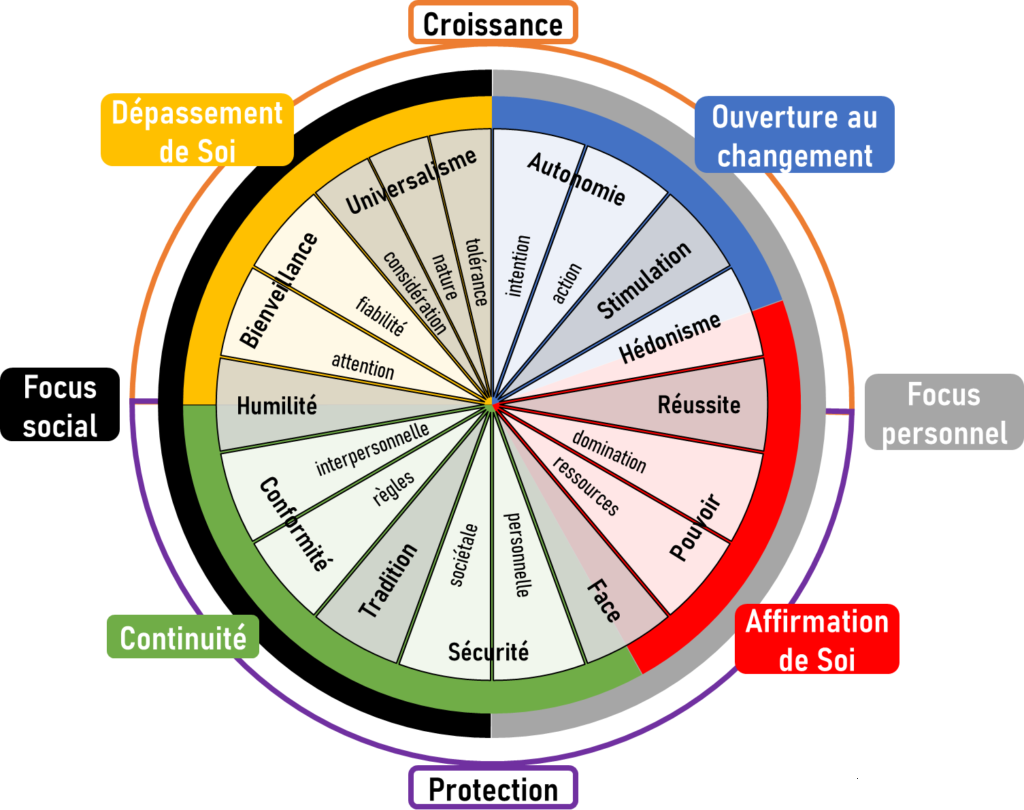

► C’est un déterminisme génétique (donc héréditaire), qui entraine, du point de vue neurologique, une mauvaise régulation de deux neurotransmetteurs principalement (excès ou carence) , la Dopamine et la Noradrénaline, notamment au niveau du lobe frontal et spécialement sa partie derrière le front, le cortex préfrontal (schéma ci-contre). – La Dopamine sert à réguler les circuits de la récompense, du plaisir, de l’énergie, de l’attention, de la vigilance et de la motivation. – Leur présence irrégulière dans les connexions entre les neurones au niveau de l’axone (schéma ci-dessus) entraine une inconsistance de l’attention, du plaisir et de la motivation, notamment pour les tâches ou les relations de la vie de tous les jours. ► Le cortex frontal sert à programmer, planifier, inhiber des comportements impulsifs, mais aussi avoir une bonne flexibilité mentale. Il doit en effet être capable de s’interrompre si quelque chose de prioritaire survient en pleine action. — Pour être attentif, on a besoin d’une bonne transmission de la dopamine dans ce cortex frontal, ce qui n’est pas souvent le cas avec le TDAH. – Cela se traduit de manière différente selon que l’on est dans une phase hyperactive ou hypoactive : – Si je suis hypoactif, c’est-à-dire avec peu d’énergie, je pense à une chose à faire qui me fait penser à autre chose, puis d’autres pensées arrivent encore. – Un haut potentiel associé à une des 8 formes formes d’intelligences recensées (mathématique, verbale, musicale, corporelle, visuelle, interpersonnelle, intrapersonnelle), peut construire une arborescence d’idées créative. – Mais souvent au final je n’ai rien fait, car je suis resté dans ma tête, et, de plus, je n’ai souvent rien mémorisé, car ce sont des pensées furtives non propices à la mémoire de travail. – Si je suis hyperactif, je commence une tâche, je l’interromps pour commencer autre chose puis autre chose sans lien avec la tâche prioritaire initialement commencée (hyperactifs). – j’ai fait une multitude de tâches ou j’ai parlé abondement, la plupart du temps sans intérêt par rapport à mes priorités et aux attentes des autres personne. ► Du point de vue neurologique, les fonctions exécutives sont regroupées en 6 familles (avec l’acronyme : A.F.F.A.M.É.E) : – ACTIVATION : s’organiser, structurer, synthétiser, prioriser, décider, initier la tâche en gérant le temps – FOCUS : maintien de l’effort et de la vitesse d’exécution, ou basculement vers une tâche prioritaire – ACTION : autorégulation des actions, ralentir, s’activer ou s’adapter selon les situations/personnes – MÉMOIRE : capacité à conserver et rappeler l’information en mémoire durant une tâche/conversation – ÉMOTIONS : savoir moduler l’émotion pour ne pas s’emporter facilement, savoir gérer la frustration – EFFORT : ne pas perdre l’intérêt dans la tâche et faire face aux difficultés dans un temps donné  ► Chacune de ces 6 familles de fonctions exécutives peut poser un problème si on a un TDAH. On parle aussi de syndrome dysexécutif. ⇒ Chacun peut faire son propre bilan neuropsychologique chez un neurologue moyennant finance, mais on peut résumer ci-dessous les principaux problèmes que rencontre la majorité des enfants et adultes TDAH : – Problèmes d’attention focalisée (concentration) et divisée (suivre plusieurs informations en simultané) – Problèmes de gestion des informations stockées dans la mémoire à court terme (mémoire de travail) – Capacité d’inhibition : il s’agit d’une difficulté à empêcher ou à freiner des comportements et paroles inadaptées. – Problèmes dans la formulation d’objectifs, l’anticipation, l’élaboration de stratégie et la prise de décision – Problèmes dans la planification, l’organisation, la gestion des priorités et la gestion du temps. ► Cette liste de déficits est insupportable pour ceux qui ont misé sur un style de vie ou un type de métier qui n’autorise pas ces dysfonctionnements. – Ces déficits des fonctions cognitives et exécutives peuvent être un obstacle si on veut construire une vie trop conventionnelle nécessitant de la rigueur et de la régularité, avec beaucoup de frustration et le sentiment de ne pas s’accomplir. – D’où la nécessité de bien se connaitre pour faire des choix de style de vie, d’objectifs et de métiers compatibles avec cette particularité neurologique, ainsi que respecter ses besoins et valeurs. – Toute forme de forte et saine motivation peut permettre de générer la dopamine et noradrénaline nécessaires pour avancer durablement sur ses projets. – Une bonne hygiène de vie, de l’exercice physique, des pratiques psychocorporelles pour calmer le mental permettront d’atténuer cette inconsistance en neurotransmetteur (voir plus loin le manuel d’auto-coaching). |